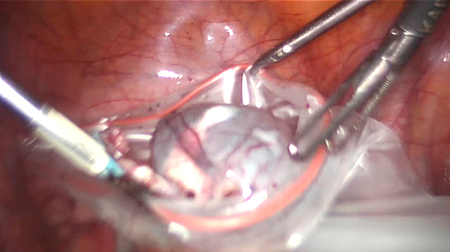

Operacijos metu rasta riestinės žarnos sąaugų su pilvo siena, iš dalies dengiančių kairiuosius gimdos priklausinius. Sąaugos išdalytos naudojant robotines žirkles. Rastas 7 cm skersmens kairės kiaušidės cistinis darinys. Dešinėje kiaušintakio nerasta. Dešinė kiaušidė ir gimda – vizualiai nepakitusios. Kairė salpingoovarektomija atlikta identiškai laparoskopinės operacijos technikai: atvertas kairysis retroperitoninis tarpas, vizualizuotas kairysis šlapimtakis, koaguliuotas ir perkirptas kairysis kiaušidės pakabinamasis raištis kartu su kiaušidės arterija ir vena (žr. 1 pav.), kairysis kiaušidės nuosavasis raištis ir kairysis kiaušintakis. Kairysis gimdos priklausinys iš pilvo ertmės pašalintas su endomaišeliu per supraumbilikalinę troakaro angą (žr. 2 pav.). Pilvo ertmė nedrenuota.

2 pav. Kairysis gimdos priklausinys iš pilvo ertmės pašalintas su endomaišeliu per supraumbilikalinę troakaro angą